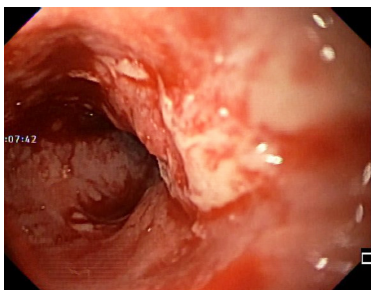

Durante la endoscopia se encuentra lengua de coloración oscura negruzca en su dorso, con aspecto de “pelos”, sin compromiso en los bordes ni en la punta, con zona de despigmentación blanquecina en la zona central posterior (Figuras 1 y 2). En el esófago medio (25 cm), por paredes laterales derecha, izquierda y anterior, hay lesión nodular, infiltrante y friable que produce estenosis franqueable de 12 mm y llega hasta los 30 cm, sin compromiso esofágico distal (Figuras 3 y 4).

Figura 3 Endoscopia. Borde proximal de carcinoma escamocelular de esófago medio que compromete el 80% de la pared y de la luz.